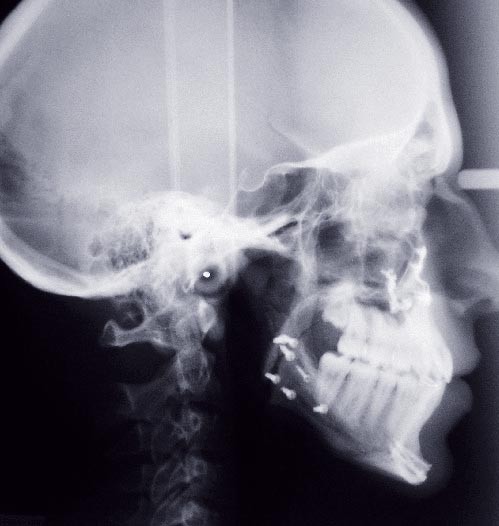

Olivier se présente à l’âge de 12 ans avec une classe III squelettique à prédominance mandibulaire, accompagnée d’une hyperdivergence et d’une endomaxillie responsable des inclusions des canines supérieures à forte obliquité. Une phase d’expansion est réalisée afin de permettre une augmentation du périmètre de l’arcade et la verticalisation des germes des canines. L’expansion permet en effet une normalisation transversale mais ne permet pas de réaliser la mise en place des canines. Les extractions des prémolaires sont alors effectuées et une préparation primaire de l’arcade supérieure par multi-attaches avec désinclusions et tractions des canines est réalisée.

Une pause thérapeutique est ensuite entamée jusqu’à la fin de croissance soit 18 ans. Une poursuite du traitement par préparation secondaire à la chirurgie orthognathique bimaxillaire est programmée.

Les mouvements de décompensations sagittales et transversales sont réalisés à l’aide des tractions inter-arcades. La réévaluation céphalométrique et l’analyse des moulages confirment l’indication d’une chirurgie maxillaire de propulsion et d’une chirurgie mandibulaire par clivage bilatéral des branches montantes pour un recul mandibulaire modéré accompagné d’une génioplastie bidimensionnelle élargie qui rappelle la technique de Chin Wing.